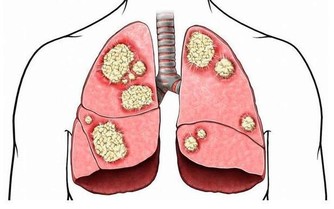

(4)防止肺栓塞和下肢深靜脈血栓形成,可皮下注射低分子肝素或肝素製劑。